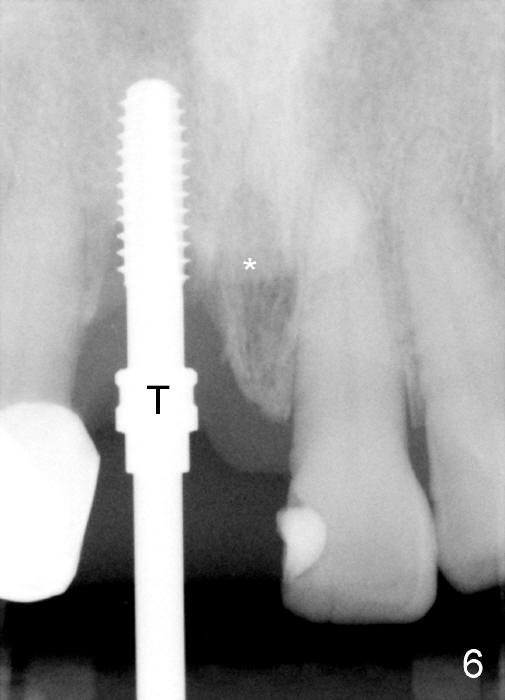

A 64-year-old lady requests replacing #7 and 8 crowns (Fig.1,2). When #8 is extracted, the labial plate is found to be missing (Fig.3). Following 2 mm pilot drill (Fig.4,5 P), 3.8 mm tap drill (Fig.6,7 T) and 4.5x14 mm implant (Fig.8 I) and 4.8 mm abutment (Fig.9 A), corticocancellous bone is harvested from the left tuberosity and placed in the labial gap of the socket (Fig.10 G). Collagen dressing is placed over the bone graft (Fig.11 C). The former is secured in place by an immediate provisional (P).

Four-month follow up shows that bone graft from the tuberosity appears to have healed with the implant microthreads (Fig.17 *); there is a diastema between #8 and 9 (arrowheads). Before removal of the provisionals of #7 and 8 for final impression, new composite is added to the mesial surface of #9 as the first step of closure of the diastema (Fig.18 <).